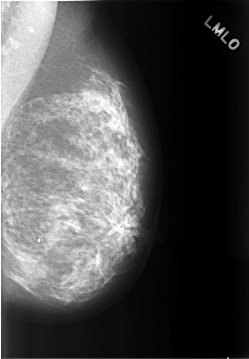

C_0307_1.LEFT_MLO

LEFT_MLO LINES 5744 PIXELS_PER_LINE 3976 BITS_PER_PIXEL 12 RESOLUTION 50 NON_OVERLAY